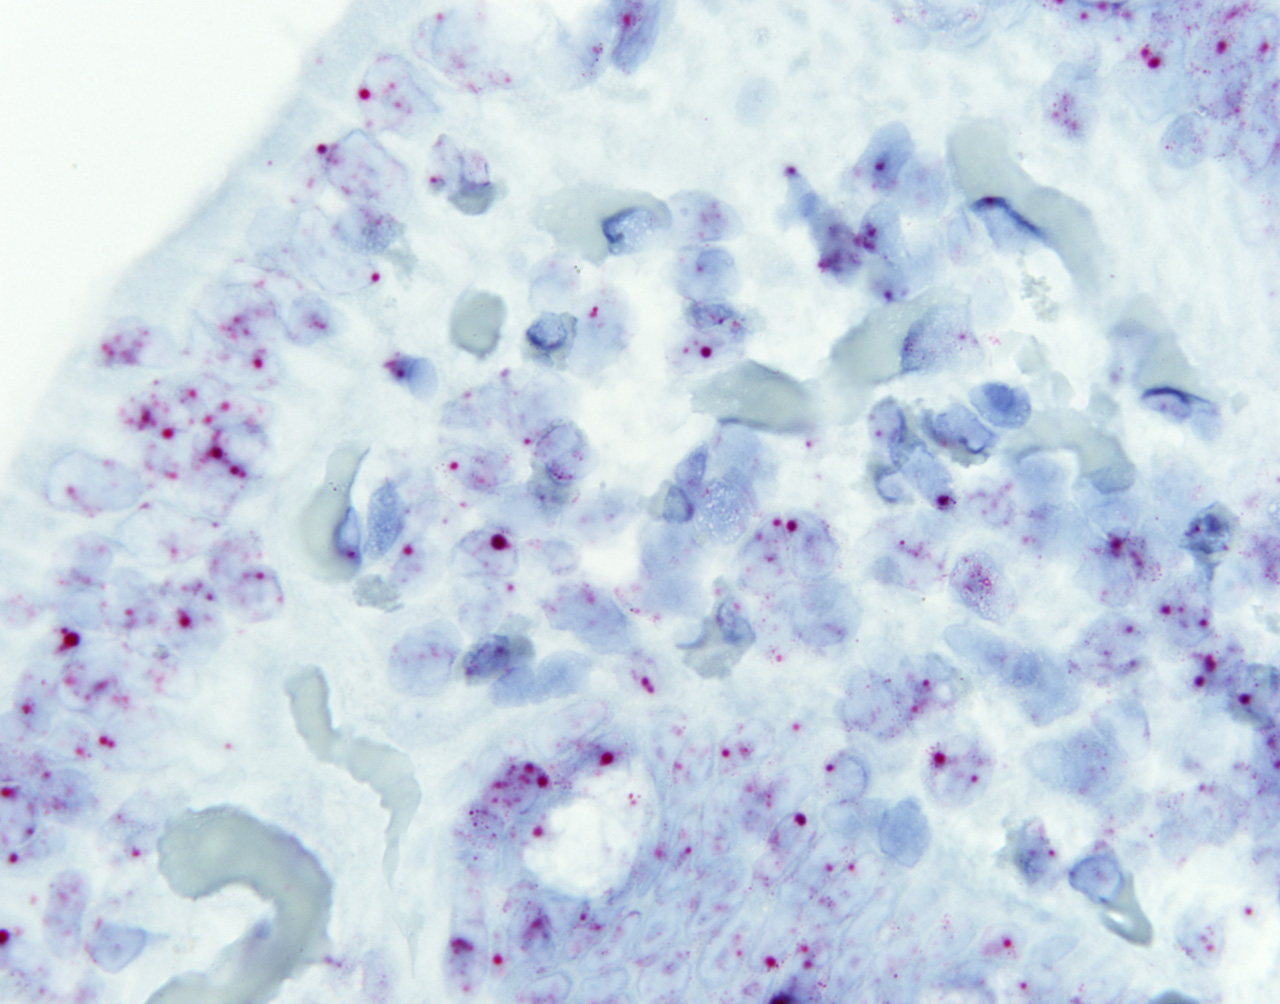

En una de estas regiones del genoma basura, han encontrado un gen clave en la regulación de la respuesta inflamatoria observada en los pacientes celíacos: es el lnc13. El ácido ribonucleico que produce ese gen pertenece a la familia de los ARN largos no codificantes (long non-coding RNA o lncRNA, en sus siglas en inglés) y se encarga de mantener los niveles normales de expresión de genes proinflamatorios. En las personas celíacas, este ARN no codificante apenas se produce, con lo que no se regulan adecuadamente los niveles de estos genes inflamatorios, que incrementan su expresión. Pero además de producirse en cantidades bajas, el lnc13 que producen los pacientes celiacos presenta una variante que altera su funcionamiento. "De esta forma se crea un ambiente inflamatorio que propicia el desarrollo de la enfermedad", indica Ainara Castellanos.

"Este estudio confirma la importancia de las regiones del genoma consideradas previamente como ‘basura' en el desarrollo de dolencias comunes como es la enfermedad celiaca, y abre la puerta a una nueva posibilidad diagnóstica. Ahora mismo estamos interesados en conocer si los niveles bajos de este ARN son una característica temprana de la celiaquía (y de otras patologías inmunes), lo que podría servir como herramienta diagnóstica antes de su aparición", explica el profesor de Genética de la UPV/EHU José Ramón Bilbao, otro de los autores del trabajo.